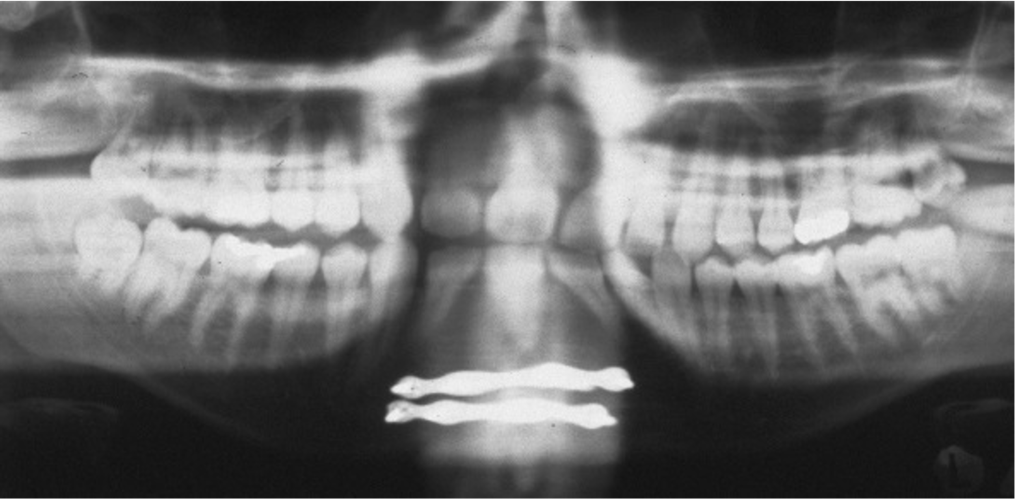

What is this positioning error?

Teeth behind focal trough

- When teeth are behind focal trough they look more enlarged – magnified horizontally

- Cant see the spine at all because its out of the focal trough